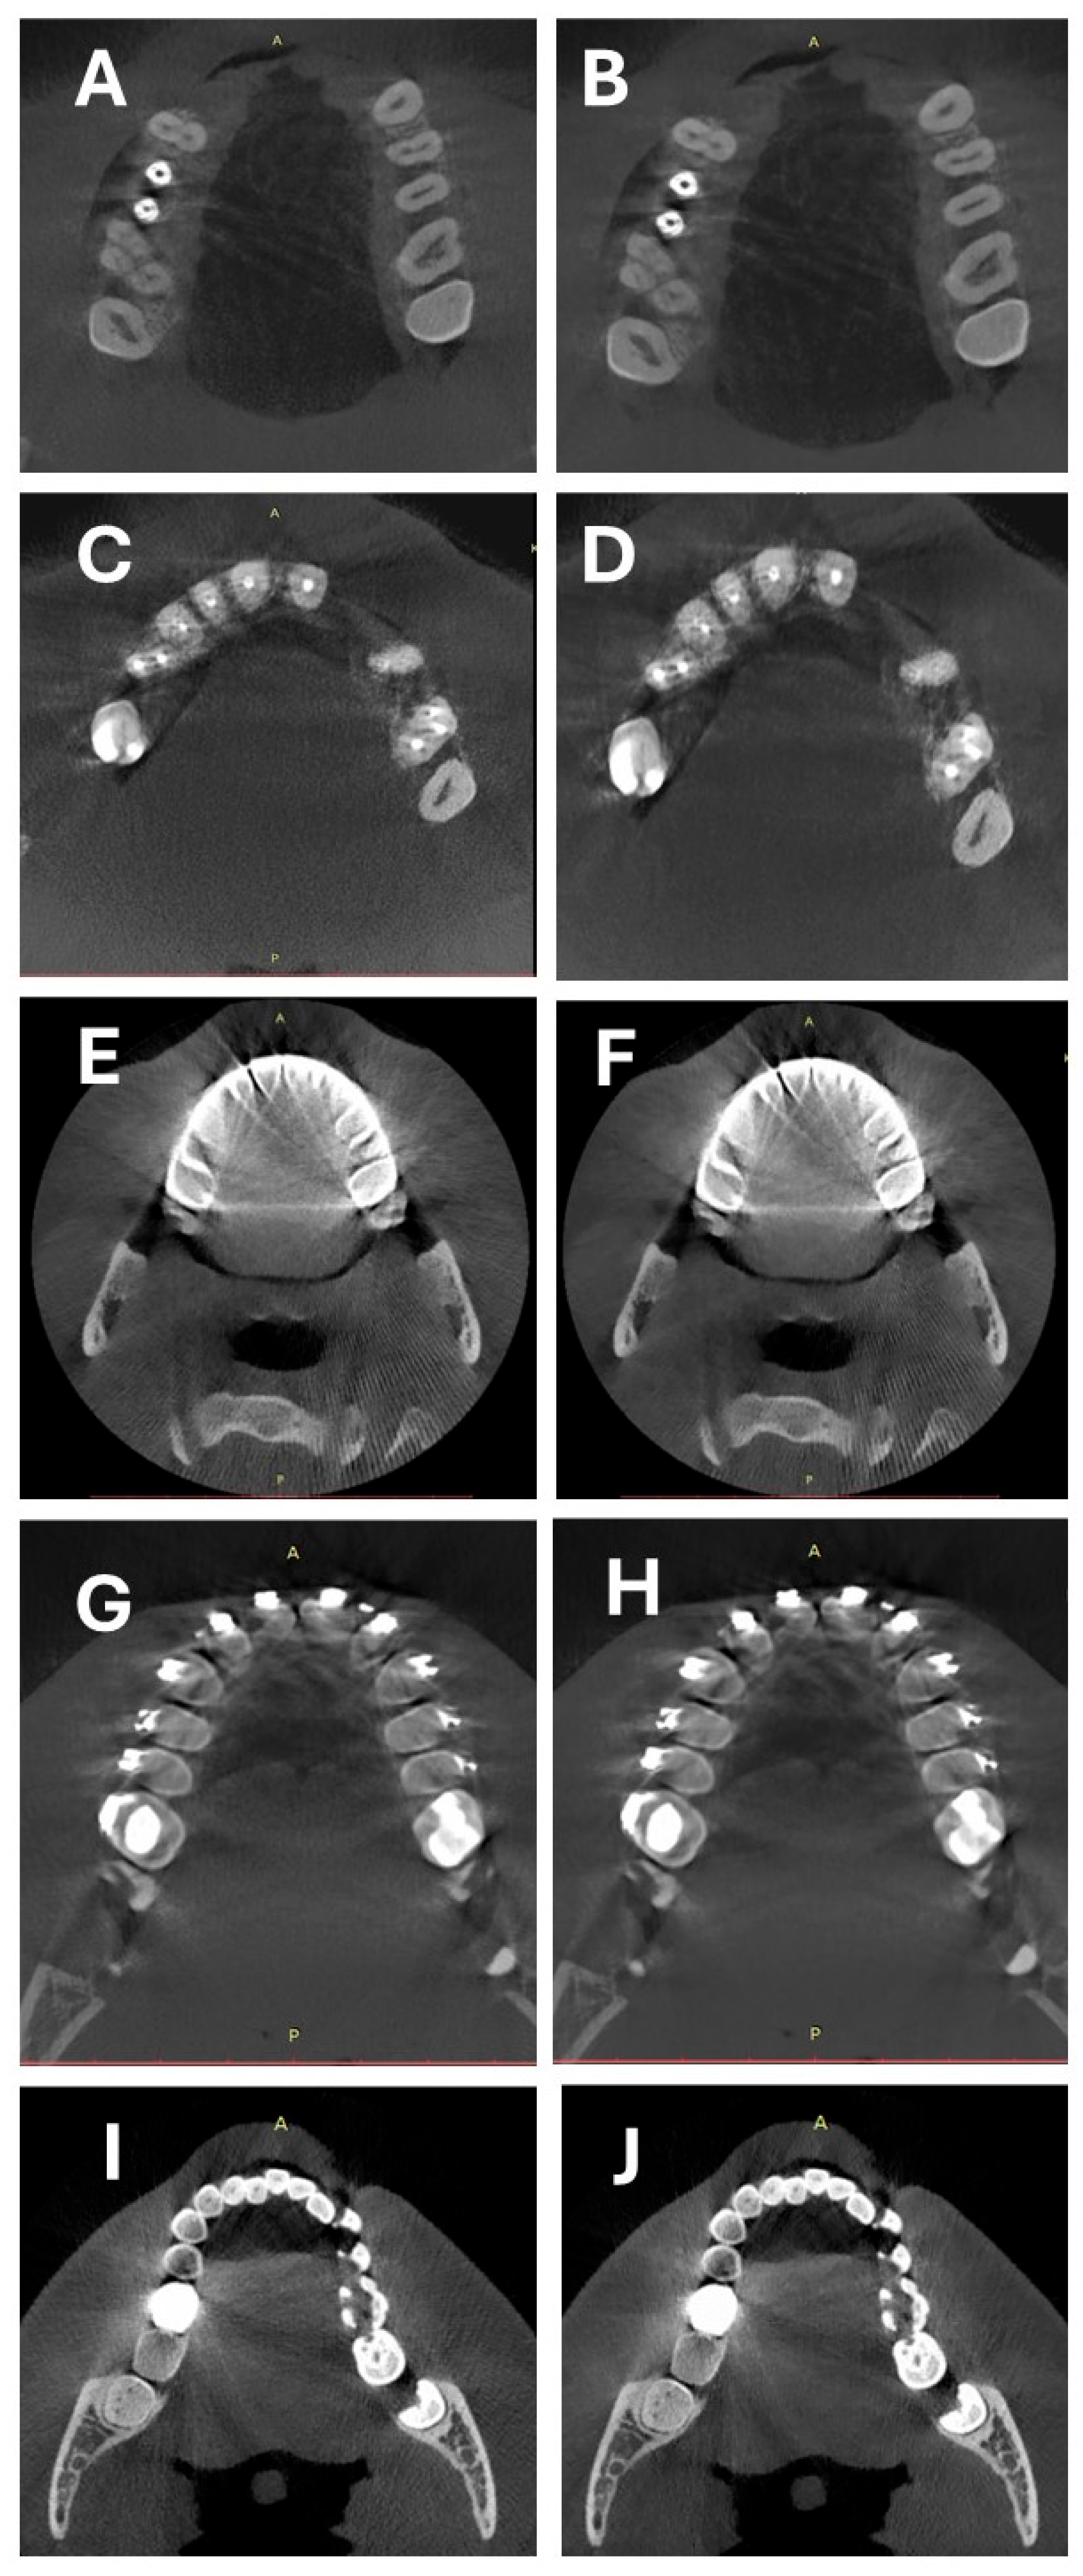

2.2. CBCT Scanning Protocol and Image Reconstruction

2.3. Objective Image Quality Assessment